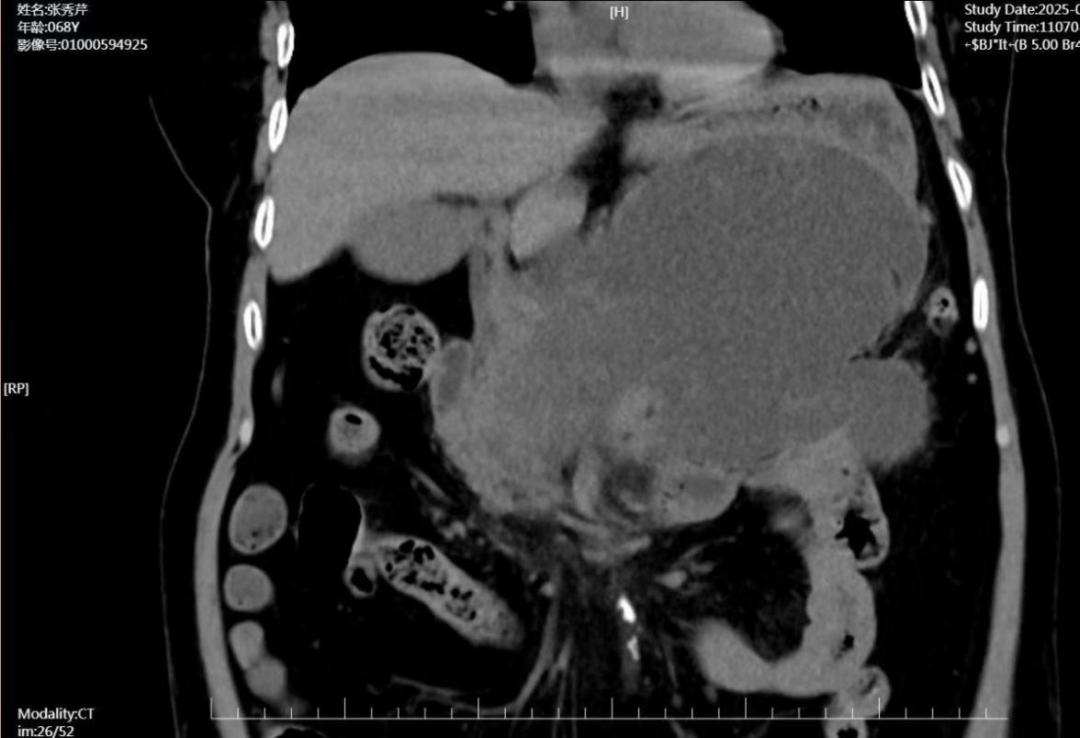

在消化内科住院期间,张奶奶仍间断出现阵发性上腹痛,查体中上腹部压痛,可触及巨大囊性包块,复查CT提示胰腺头颈体尾部见囊片状低密度影,临近胰腺、胃腔受压推移明显,最大直径达15.7cmX9.2cm;结合患者病史,考虑疾病早期形成大量渗出吸收不良,形成包裹性坏死可能。

术前CT提示所见胰周巨大包裹性坏死

术后复查CT提示胰周包裹性坏死明显缩小